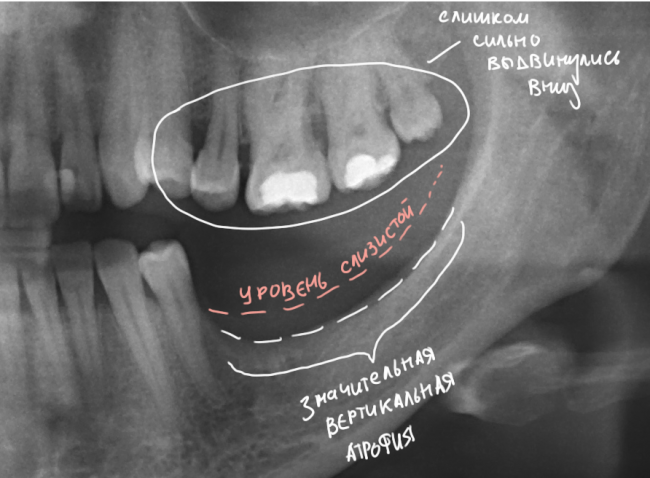

Итак, вот изначальная ситуация:

до лечения

Я понимаю, что данных на части панорамного снимка очень мало для правильной интерпретации клинической ситуации, но, с другой стороны, это позволит не перегрузить Вас информацией.

• боковой сегмент, отсутствуют три зуба: 35, 36, 37. Эти зубы удалены достаточно давно, развилась сильная атрофия костной ткани.

• верхние зубы, не имея антагонистов, выдвинулись вниз (зубоальвеолярное удлинение, т. н. «симптом Попова-Годона»).

• пациентке примерно 30 лет. То есть, вся жизнь еще впереди)).

Sketch94233528

Их несколько, они обозначены на снимке.

1. Значительная атрофия костной ткани, особенно по высоте. Решается: остеопластической операцией.

2. Дефицит слизистой оболочки почти всегда сопровождает атрофию кости. Следовательно, после имплантации (либо до нее) нам потребуется пластика десны. Я предпочитаю это делать на этапе установки формирователей десны.

3. Зубоальвеолярное удлинение в области зубов-антагонистов. Решается: ортодонтическим лечением.